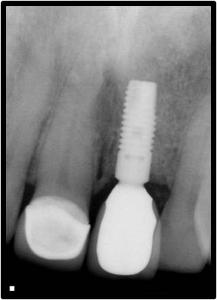

Pre-op and Post-op of implant placed at #9

Before

After